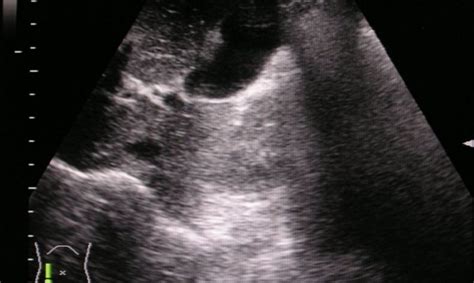

Adenomyóza je ochorenie, pri ktorom tkanivo vystielajúce dutinu maternice (endometrium) začne prerastať do hrúbky jej svalovej vrstvy (myometrium). V dôsledku toho sa bunkové štruktúry endometria ocitnú vnútri svalu, kde naďalej reagujú na hormonálne zmeny počas menštruačného cyklu. Rast tkaniva vedie k zahusteniu stien maternice, zápalovej reakcii, opuchu a časom k vzniku uzlín, fibrózy a zvýšenej citlivosti.

- Myometrium: Hrúbka svalovej vrstvy maternice.

Riziká adenomyózy zahŕňajú chronickú bolesť, silnú a dlhotrvajúcu menštruáciu, ktorá vedie k anémii, a tiež zhoršenie reprodukčných funkcií, čo sťažuje počatie a zvyšuje riziko potratu. V závažných prípadoch vedú chronický zápal a štrukturálne zmeny k zníženej funkcii maternice a výraznému zhoršeniu kvality života.